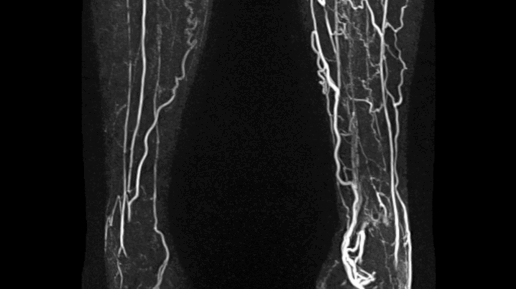

Постромботическая болезнь (ПТБ или ПТФС) — заболевание развивающееся как следствие перенесенного тромбоза вен нижних конечностей, в результате которой произошло повреждение клапанов вены и нарушение оттока крови по магистральным (основным) венам нижней конечности. ⠀ ☝️Далеко не каждый тромбоз глубоких вен приводит к развитию ПострТромботической Болезни! ⠀ ❗Однако при отсутствии своевременного лечения риск развития ПТБ увеличивается до 50%. ⠀ У 4-х пациентов из 5-ти, трофические язвы ног развиваются как следствие перенесенного тромбоза вен...